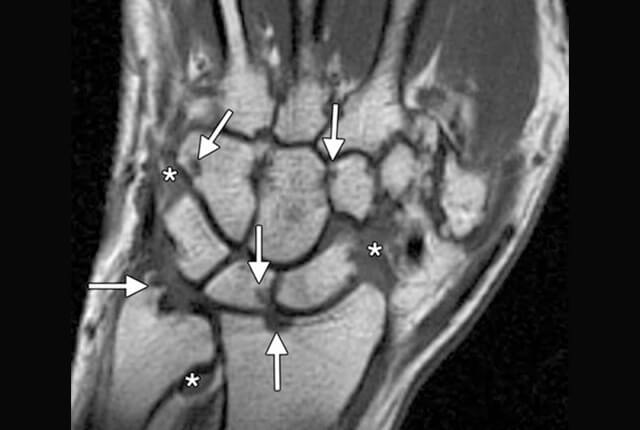

• MRI:滑膜炎、骨びらん、関節破壊を早期に発見できます。当院ではオープン型MRIを完備しています。

MRI